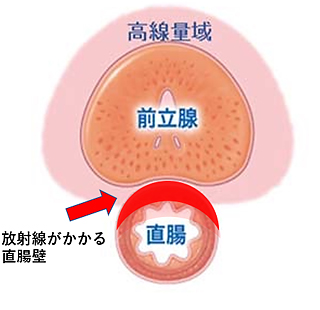

放射線治療の場合、がんのある前立腺のみに照射したいのですが、前立腺は上に膀胱、後ろに直腸が接しているため、従来の外部照射療法では前立腺だけでなく周辺の臓器にも多くの線量の放射線がかかってしまい、また密封小線源治療(シード治療)でもある程度の線量がかかってしまい、かかったところに有害事象(副作用)が出現していました。

その一つが、直腸、膀胱の有害事象で、直腸出血、直腸粘膜の潰瘍や出血、肛門痛、下痢、膀胱・尿道への影響、勃起障害であり、まれに直腸尿道ろう(直腸と前立腺の間にろう孔ができてしまう)ような重篤な合併症が発生することがあります。

SpaceOAR®システム留置なし

(赤い部分)、直腸の合併症が出現します。

前立腺への総線量72Gy > 直腸の耐容線量60Gy